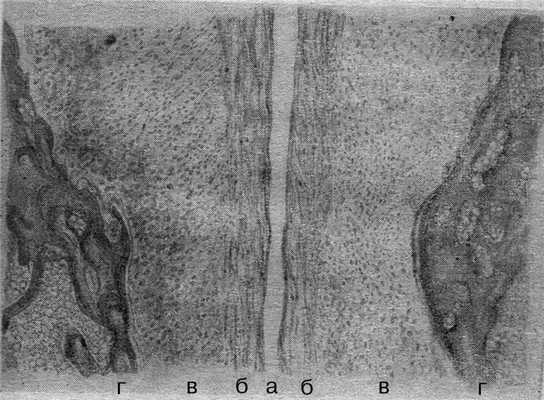

Одно из наиболее детальных описаний морфологии ЛС приведено М.Ф. Айзенбергом (1962). По его данным, ЛС «обладает половыми особенностями и имеет индивидуальные различия. Наблюдаются все виды соединений - от синхондроза до настоящего сустава. У детей и лиц мужского пола ЛС представлено чаще в виде бессуставного сращения - симфиза. Появление же щели в центре фиброзного хряща, делающей его несколько подвижным, превращает это соединение в так называемый полусустав. В тех случаях, когда щель проходит через всю высоту и толщину фиброзного хряща и смыкается с периферическими связками, соединение становится подвижным. Особенности строения и состояния лонного сочленения у женщин, безусловно, находятся в тесной связи с эндокринными и функциональными процессами, происходящими в организме». По данным М.Ф. Айзенберга (1962), морфологически хрящевая межлобковая пластинка неоднородна: большая ее часть представлена гиалиновым хрящом, по периферии от межлобковой щели расположена зона фиброзного хряща. С возрастом гиалиновый хрящ вытесняется и в ряде случаев определяется в виде отдельных островков (рис. 2). Рисунок 2. Морфология лонного сочленения у пациентки фертильного возраста (по М.Ф. Айзенбергу). а - щель лонного сочленения; б - фиброзный хрящ; в - гиалиновый хрящ; г - кость.